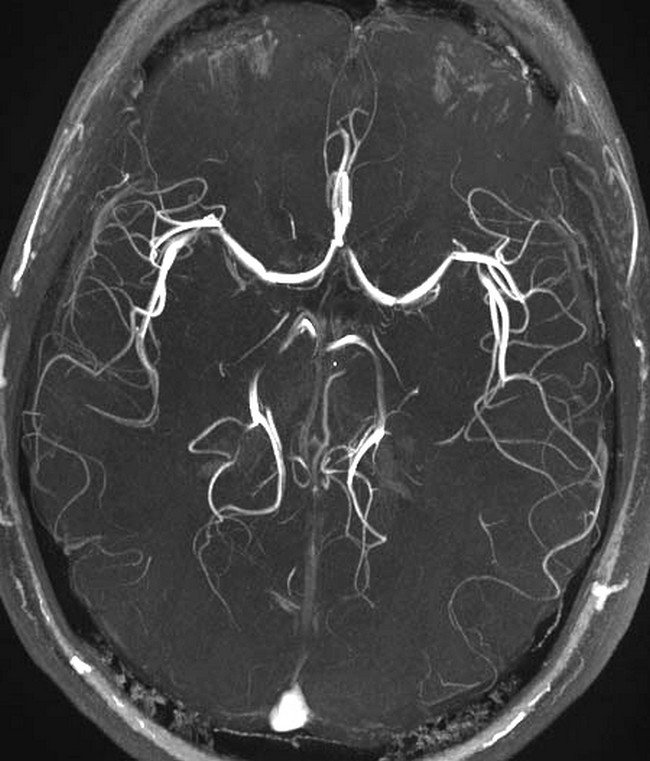

Trong chụp não, MRI có thể phân biệt rõ ràng phần chất trắng và chất xám của não cũng như có thể được sử dụng để chẩn đoán phình mạch và phát hiện sự có mặt của các khối u. Do chụp cộng hưởng từ không sử dụng các bức xạ ion hóa nến đây là phương pháp chẩn đoán được lựa chọn khi cần thường xuyên theo dõi hình ảnh của não trong quá trình điều trị. Tuy nhiên chi phí cho chụp cộng hưởng từ lớn hơn nhiều so với chụp X-quang hay chụp cắt lớp vi tính.

- Chụp MRI tại Vinmec có thể chụp tái tạo mạch máu 3 chiều không cần tiêm thuốc tương phản, có thể chụp tái tạo và xử lý các xảo ảnh chuyển động của bệnh nhân